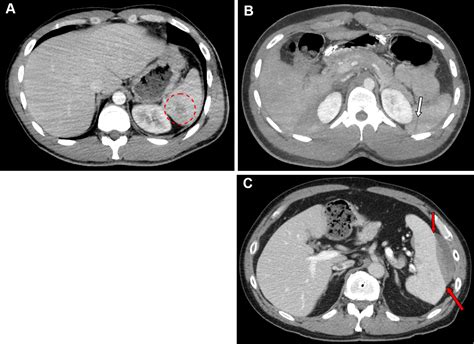

• Imaging Tests: Imaging tests such as CT scans are crucial for visualizing the spleen and assessing the extent of the injury. These tests provide detailed images that help in Splenic Laceration Grading.